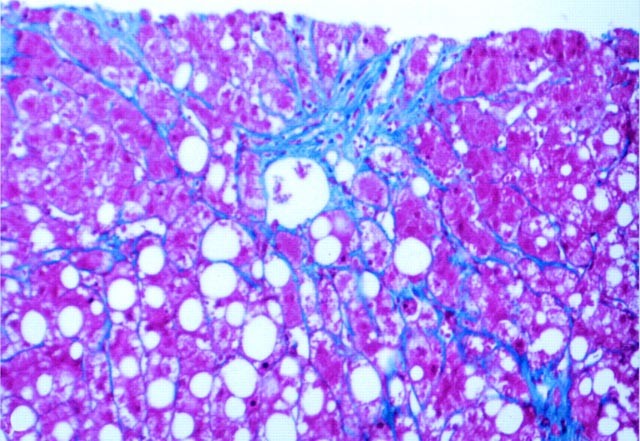

Figures 1, 2 and 3 illustrate lesions of steatohepatitis in cases of primary biliary cirrhosis, α-1-AT, and hepatitis C, respectively.

A andB, AMA-positive PBC. Many of the lesions of steatohepatitis, including mixed steatosis, ballooning, and mixed lobular acute and chronic inflammation are noted in the hematoxylin and eosin stain (A); the trichrome section (B) shows the characteristic persinusoidal fibrosis in zone 3 (upper left). The portal tract (lower right) is also expanded by fibrosis, presumably due to the primary biliary cirrhosis (A, H&E, 20 ×;B, Masson’s trichrome, 10 ×).